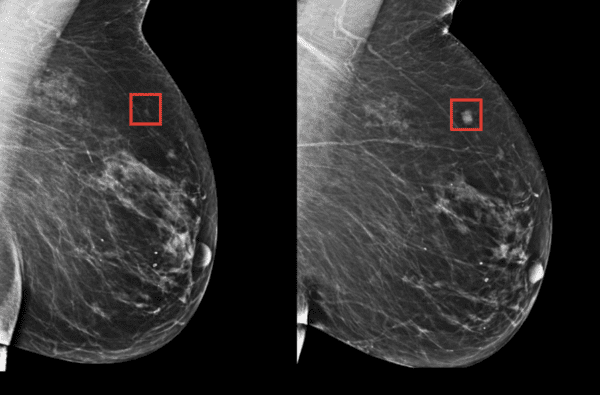

Uma nova inteligência artificial pode detectar o câncer de mama 5 anos antes de ele se desenvolver - Escola de Lucifer

Que bom que se pode usar ferramentas de IA para detectar anormalidades com eficiência ajudando na prevenção de câncer de mama, assim facilita a tratamentos antecipados. LPN